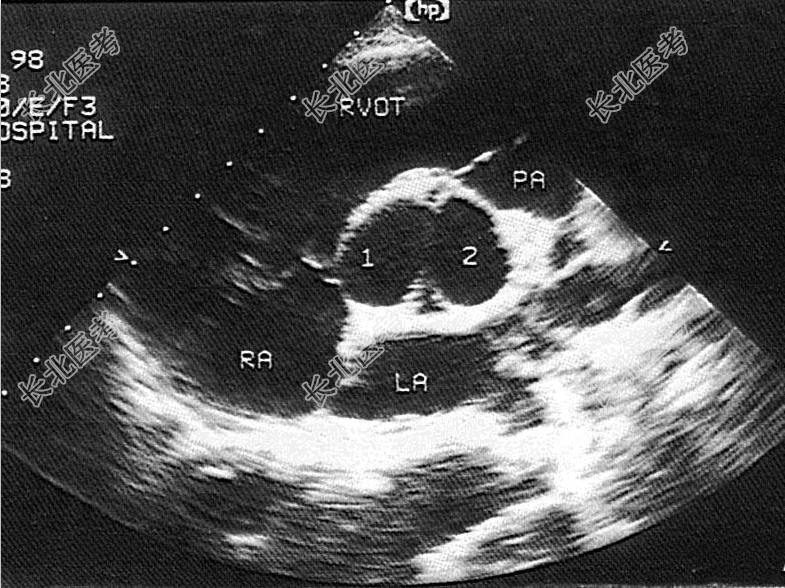

- 单项选择题该病例超声检查如图,最可能的诊断是

A、主动脉二叶瓣

B、主动脉单瓣

C、主动脉四叶瓣

D、主动脉三叶瓣

E、主动脉五叶瓣